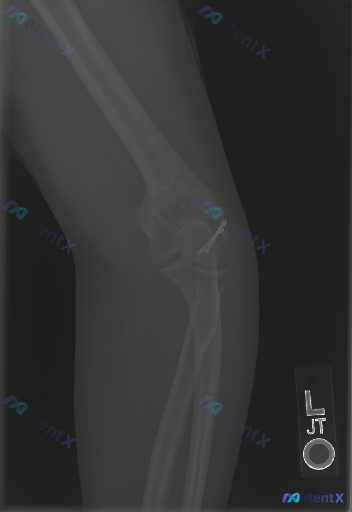

左肘关节术后X光复查,除了内固定物,这个细节别忽略

- 基础情况:左肘关节侧位片,标记L

- 明确发现:肱骨小头/外髁区域有金属内固定物(高密度影,考虑克氏针或微型螺钉)

- 骨骼整体:对位良好,关节关系正常,未见新的骨折线

- 容易被忽略的点:报告提了一句「肘关节前方软组织影密度稍高」,但后脂肪垫征不明显